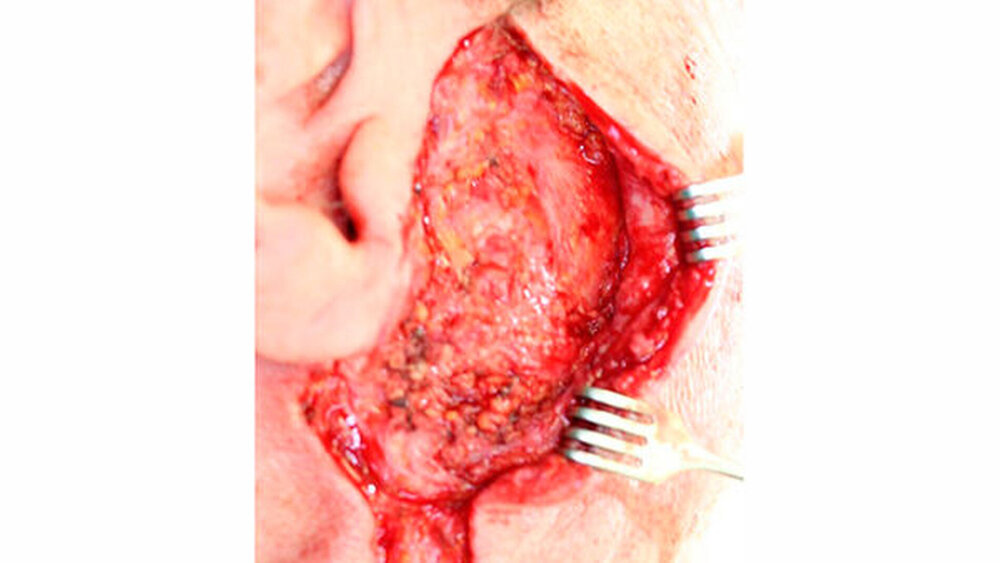

Es wurde die erneute OP-Indikation zur Vergrößerung des Sicherheitsabstandes im Sinne einer partiellen Parotidektomie sowie einer prophylaktischen ipsilateralen Neck dissektion der Level I und II gestellt (Abbildung 3). Abbildung 4 zeigt das Nachresektat. Postoperativ lag kein Hinweis auf eine Schädigung des N. facialis vor. Bei sanatio per primam intentionem entließen wir den Patienten am fünften postoperativen Tag in die ambulante Nachsorge. Die abschließende Histologie ergab weder Residuen des resezierten myoepithelialen Karzinoms noch einen Lymphknotenbefall (TNM-Klassifikation (8. Auflage): pT2, pN0 (0/9), G3, R0).